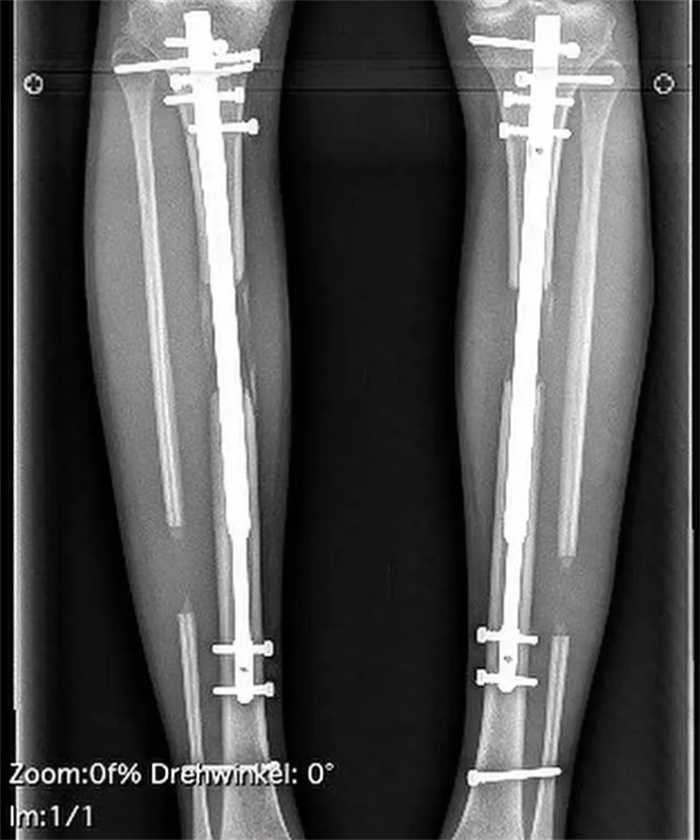

第一次手术,他的胫骨和腓骨被打断,然后挖空了胫骨内部,取出骨髓,再将一根钢杆放入骨头内(可伸缩),用螺钉将其固定。最后还要用钉子将骨头和外部的仪器固定。

手术后需要坐在轮椅上,而且每天都要进行痛苦的腿骨分离训练。

每天,布莱恩都要用扳手旋转腿部的固定器4次,试图将断开的骨头一点点分开。据介绍,这样硬生生将骨头分开的旋转,10次才能增加0.5毫米。

康复的时间长短因人而异,布莱恩花了2个多月的时间做复健。12月份手术,2月份才拆除固定器,结果他长高了约三英寸。